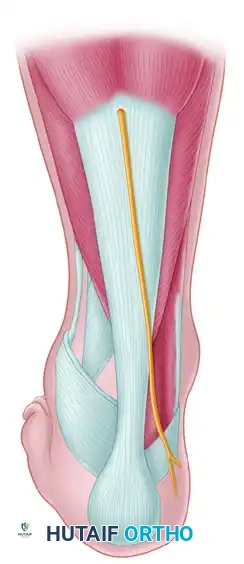

3. The Posterolateral Approach

For the placement of posterior-to-anterior (PA) screws—which are biomechanically superior due to the denser bone of the posterior talar body—a posterolateral approach is utilized.

- Positioning: The patient may need to be in a lateral or prone position, though a floppy lateral position can sometimes accommodate both anterior and posterior access.

- Incision: Utilize the Henry approach from the lateral side of the Achilles tendon.

- Interval: Develop the interval between the flexor hallucis longus (FHL) medially and the peroneal tendons laterally. Retracting the FHL medially protects the posteromedial neurovascular bundle.

Posterior-to-Anterior (PA) Screw Fixation:

* Place the guidewire above the lateral projection of the posterior process.

* Direct the wire anteriorly toward the lateral talar head.

* Fluoroscopic guidance is essential to avoid penetrating the subtalar joint.